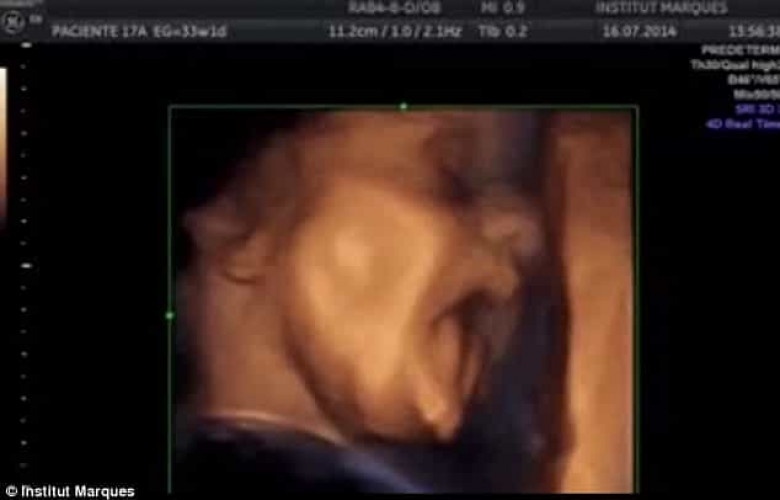

Բժիշկները ցույց են տվել՝ ինչպես է պտուղը «երգում» մոր արգանդում (լուսանկարներ)

ԼԱՅՖԲժիշկների անցկացրած նորագույն ուսումնասիրության արդյունքները փաստում են, որ մայրական արգանդում գտնվող պտուղն ունակ է լսել արտաքին ձայներն արդեն 16 շաբաթականում:

Ինչպես նշում է The Daily Mail-ը, Բարսելոնայի Մարկեսի անվան համալսարանի գիտական թիմն ապացուցել է, որ պտուղն ունակ է ոչ միայն լսել ձայները, այլև` դիմախաղով ու բերանի շարժումներով արձագանքել դրան։ Ըստ մասնագետների՝ պտղի նման պահվածքը ենթադրում է, որ նա «երգում» է։

Աղբյուրը մանրամասնում է, որ նախկինում բժիշկները կարծում էին, որ պտուղը սկսում է լսել միայն 16-26 շաբաթականում։